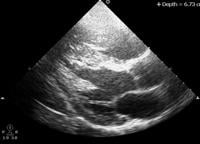

The April issue of the Journal of the American Society of Echocardiography (JASE) features a compilation of the discussion at the summit. The article, entitled “A Suggested Roadmap for Cardiovascular Ultrasound Research for the Future,” reflects discussion of a selected range of issues relating to the assessment of global and regional left ventricular function, regional myocardial perfusion, molecular imaging, therapeutic ultrasound, and peripheral vascular imaging. The summary article is available on the Research Resources page of the ASE website.